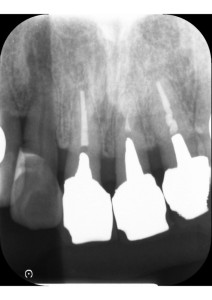

エックス線で撮影したところ、患者様は歯周病も進行しており、全体的に骨が吸収して歯根の半分まで減ってしまっていました。

特に、左右7番の骨が著しく減っており、左上の奥歯は歯根まで骨が吸収し、残すことが不可能な状態でした。

2日目 左上7の抜歯を行いました。抜歯した左上7番目は、CTを撮影したところ骨の高さがないことがわかりました。また、左上6番目のインプラントが左下7番と咬んでおり、噛み合わせでのバランスは保たれていることから、インプラントは行わずに現状維持となりました。

ただし、患者様は前歯がワイヤーで固定されており、インプラントの被せ物が繋がっているため、歯間ブラシやフロスの使用はとても難しい状態です。複雑な構造物になるほど、治療後のお口のケアは難易度が増していきます。